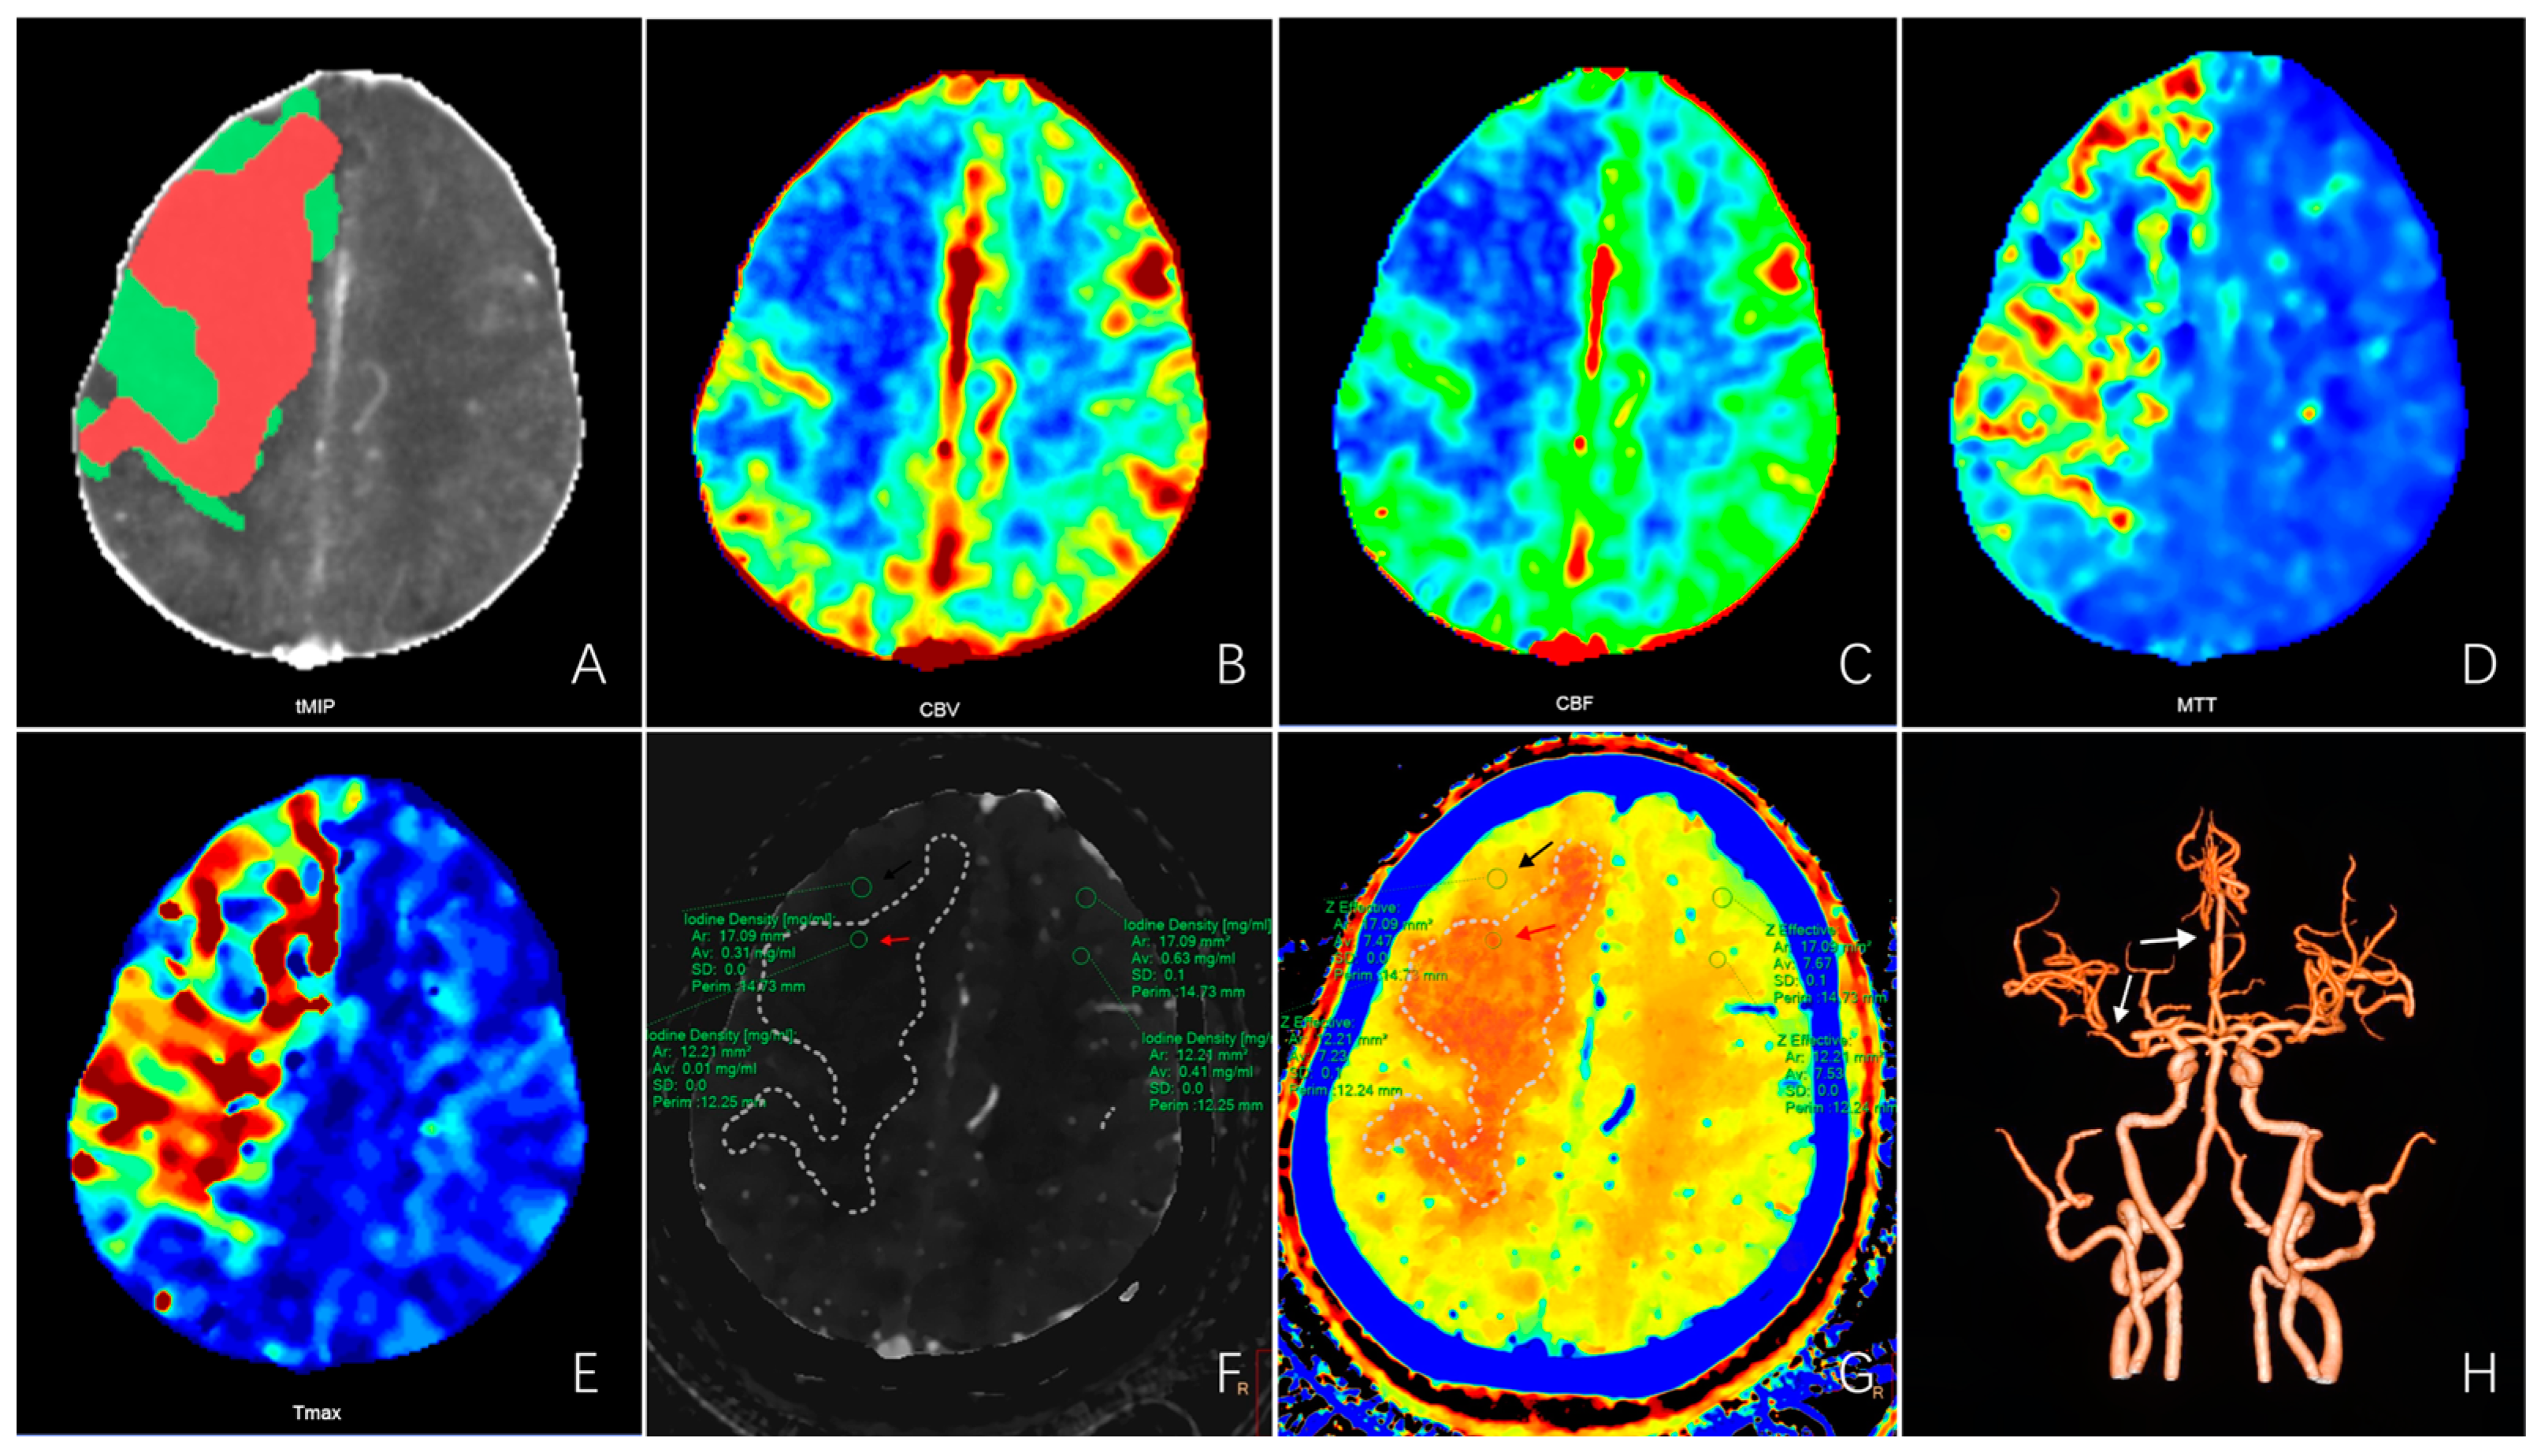

3.2. Cut-Off Values for Iodine Density and Effective Atomic Number

3.3. Univariate and Multivariate Logistic Analyses of Clinical and Spectral CT Parameters

3.4. Development and Performance of the Prognostic Nomogram